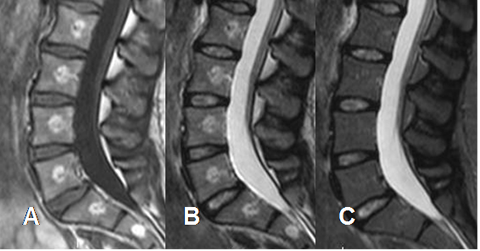

Fig 153. Hemangiomas múltiples.

A: RM sagital en T1, B: RM sagital en T2 y C: RM sagital en STIR. Múltiples hemangiomas vertebrales y en el sacro, que suprimen en el STIR.